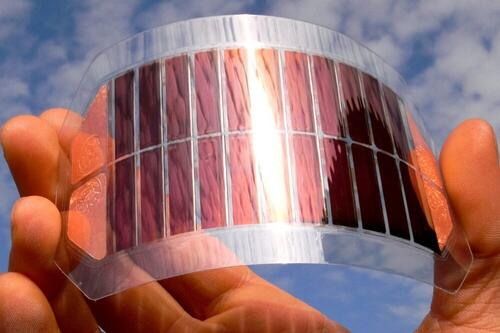

Основой биомиметической конструкции является гибридный каркас из сверхвысокомолекулярного полиэтилена, формирующего внутренний пористый и внешние сплошные слои, воспроизводящего макроструктуру костей млекопитающих, и титанового армирующего компонента. Для изготовления имплантата используется сверхвысокомолекулярный полиэтилен и гидроксилапатит — минеральная составляющая костной ткани. Для имитации пор трабекулярной кости в материал вводится соль высокой степени очистки. На специальном оборудовании и в определенных режимах смесь прессуют в монолитный материал. Затем под большим давлением и при высокой температуре из него вымывают соль водой, сохраняющей жидкое состояние при температуре от 100°С и давлении от 218 атмосфер (субкритическая вода).

В верхние непористые слои имплантата с помощью сверхкритических сред вводится антибактериальный компонент, который позволит защитить организм от проникновения инфекции в место имплантации и избежать воспалений. Пористую часть имплантата насыщают клетками, взятыми из костного мозга пациента, и белками, стимулирующими новообразование костной ткани в области имплантации.